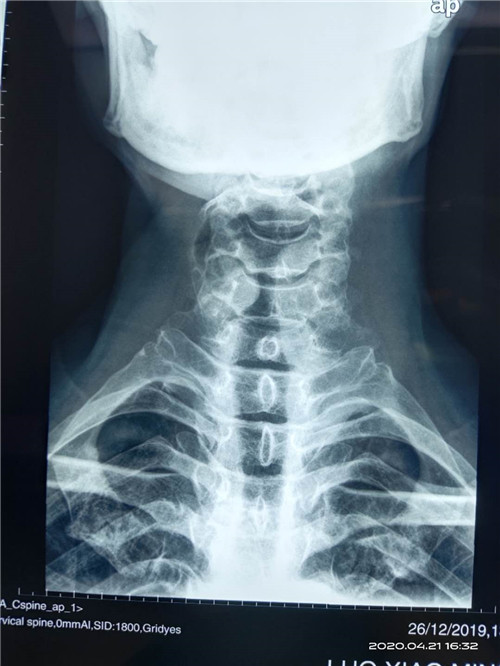

近日,昆明市延安医院呈贡医院(呈贡区人民医院、呈贡区中医医院)外一科为一位寰枢关节脱位患者成功实施了后入路颈1、2复位椎弓根螺钉内固定手术,患者术前诊断为:“寰枢关节脱位”。曾到过省内多家大医院就诊,因害怕手术风险,未敢做手术,后慕名前来我院,外一科主任杨旭民主任医师仔细查看患者及相关资料后收住院,并与患者及家属耐心讲解病情及手术方法、手术风险后,患者同意在我院手术,经过术前准备后于4月21日外一科在杨旭民主任带领下为患者成功实施了后入路颈1、2复位椎弓根螺钉内固定手术。术后患者寰枢关节脱位完全复位,固定满意。于4月22日由ICU安全转回普通病房。

术前图片如下:

微信图片_20200507143049